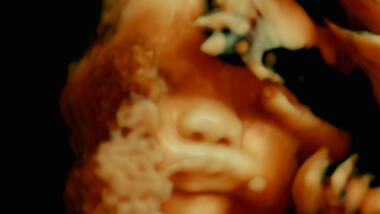

Les merTidligere har regissørene Lucien Castaing-Taylor og Véréna Paravel fascinert en hel verden med sine banebrytende skildringer av fiskeindustri i Leviathan (2012) og kannibalisme i Caniba (2017). Nå er de tilbake med en minst like grensesprengende dokumentar, og denne gangen har de observert arbeidshverdagen ved ulike sykehus i Frankrike. Over 350 timer med opptak er blitt klippet ned til en unik film, som dykker langt inn i menneskekroppens gåtefulle indre.

Filmen, som har samme tittel som Andreas Vesalius’ viktige lærebok om anatomi fra 1543, tar deg med på en oppdagelsesferd i et landskap som er ukjent for de fleste. Sjelden har kroppen blitt portrettert så ærlig og direkte på film. NB! Filmen passer definitivt ikke for sarte sjeler.